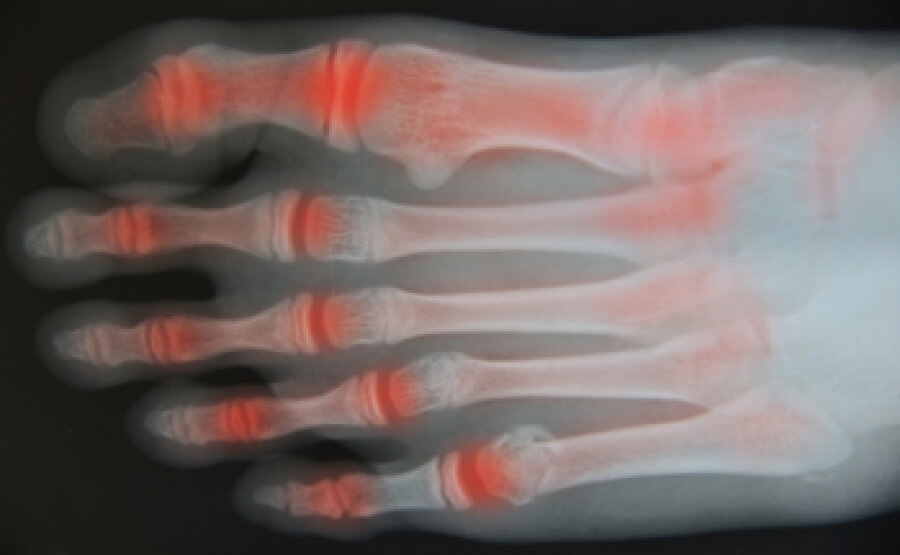

Exercise For Feet With Arthritis . these exercises are helpful for problems and pain affecting the toes, feet and ankles. The exercises may be suggested for a condition or for rehabilitation. Remember to drink water while you're. exercises for arthritis might include exercises that put joints through their full range of motion and strengthening. here are some examples of exercises for you to try. feet & ankle exercises. sit in a chair and lift your foot slightly off the ground. Keep the muscles in your feet and around your ankles fit and flexible with these simple and effective.